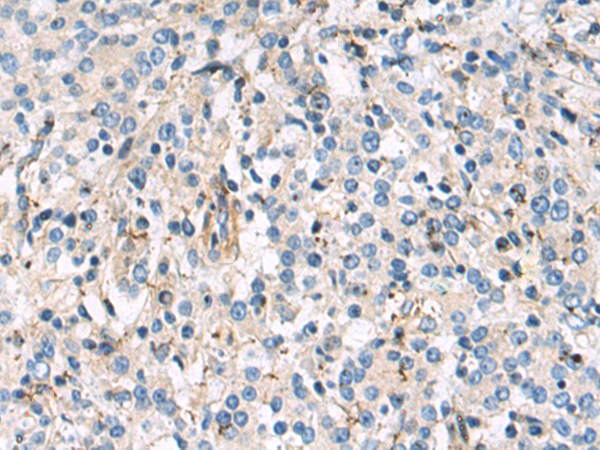

分类: 科研抗体货号: P10614别名: RIF; ARHF应用: WB,IHC反应种属: Human, Mouse

分类: 科研抗体货号: P10598别名: RCH2; SRP1; IPOA5; NPI-1应用: IHC反应种属: Human, Mouse, Rat

分类: 科研抗体货号: P10607别名: Prp5; PRPF5应用: IHC反应种属: Human, Mouse, Rat

分类: 科研抗体货号: P10606别名:应用: WB,IHC反应种属: Human

分类: 科研抗体货号: P10612别名: AMY-1应用: IHC反应种属: Human, Mouse

分类: 科研抗体货号: P10611别名: PDF; PFD1应用: IHC反应种属: Human, Mouse

分类: 科研抗体货号: P10605别名: CMT2Q; AMOXAD应用: IHC反应种属: Human, Rat

分类: 科研抗体货号: P10610别名: LIP1; LIP.1; LIPRIN应用: IHC反应种属: Human